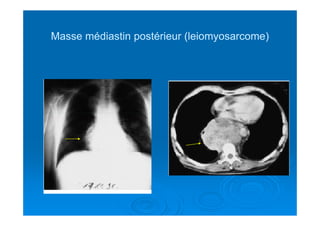

Masse médiastin postérieur (leiomyosarcome)Masse médiastin postérieur (leiomyosarcome)

Masse médiastin postérieur(leiomyosarcome)Masse médiastin postérieur (leiomyosarcome)